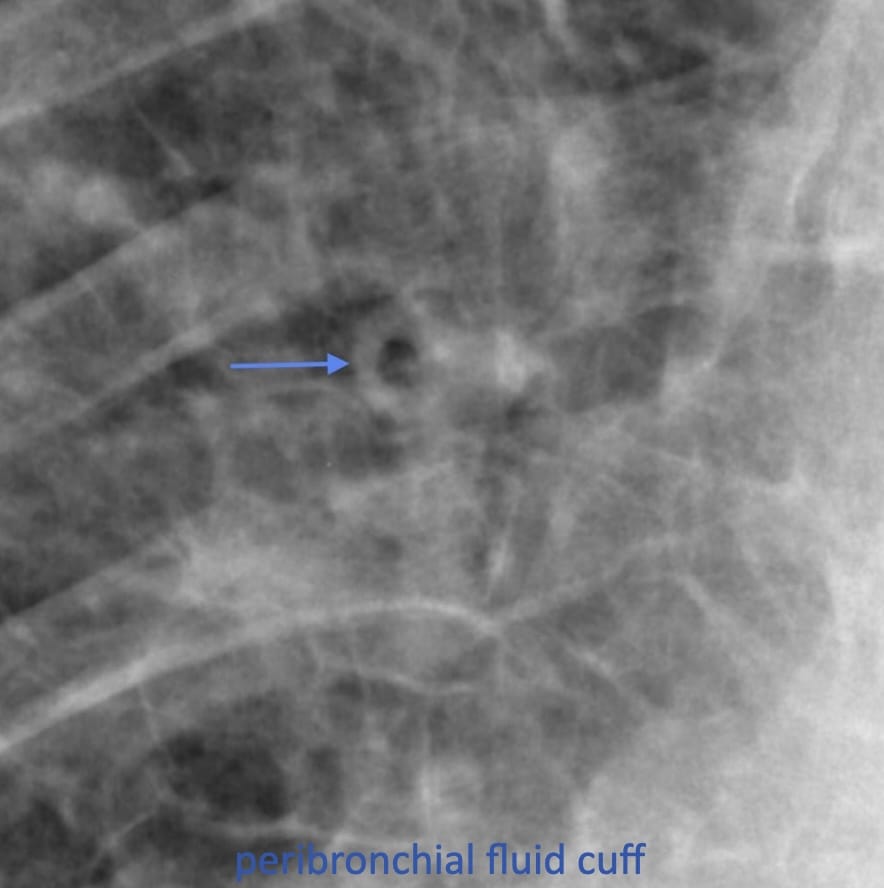

Peri-bronchial fluid cuff

The broncho-arterial bundle—bronchi and arteries run together—is surrounded by a connective tissue sheath This is shown in this animal model-derived micrograph, before and after it is filled with water (***), with a corresponding CT image alongside.